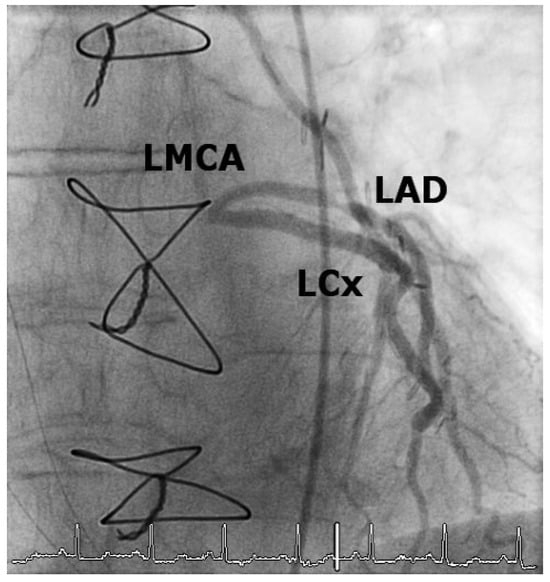

Iatrogenic Left Main Stem Stenosis After Surgical Aortic Valve Replacement

by Jens Robert, David Tüller and Stephan Windecker

Cardiovasc. Med. 2011, 14(3), 101; https://doi.org/10.4414/cvm.2011.01578 - 23 Mar 2011

Surgical aortic valve replacement (SAVR) represents the gold standard in the treatment of symptomatic severe aortic valve stenosis as reflected by the class I indication assigned in the ACC/AHA and ESC guidelines. SAVR effectively relieves symptoms, improves quality of life as well as [...] Read more.

Surgical aortic valve replacement (SAVR) represents the gold standard in the treatment of symptomatic severe aortic valve stenosis as reflected by the class I indication assigned in the ACC/AHA and ESC guidelines. SAVR effectively relieves symptoms, improves quality of life as well as prognosis of affected patients. As with any therapeutic intervention, SAVR is associated with some short and long term adverse events including death, stroke, myocardial infarction, renal failure, bleeding, as well as structural and non-structural valve deterioration. We present two cases of iatrogenic left main stemstenosis within less than one year after SAVR, describe the management and discuss the literature. Full article